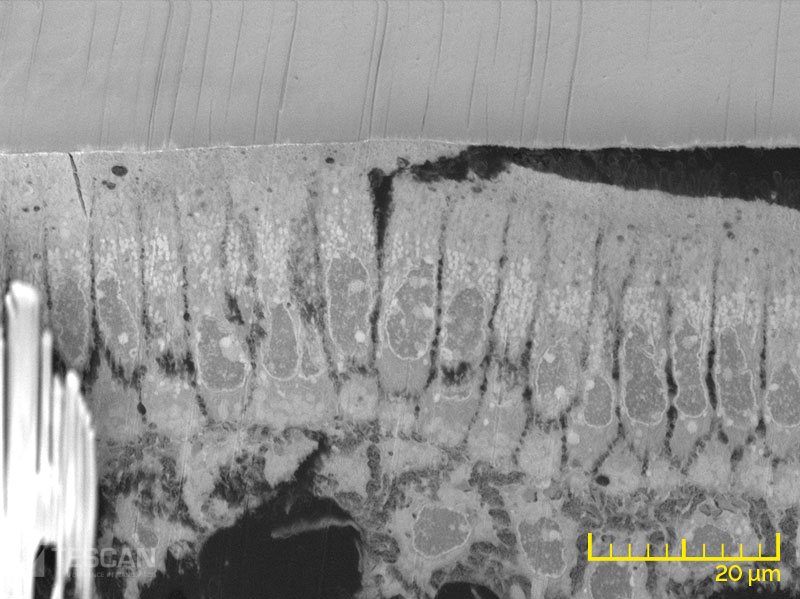

Osteoblast layer in a mouse tooth (chụp bằng Kính hiển vi điện tử quét SEM, FIB-SEM TESCAN)